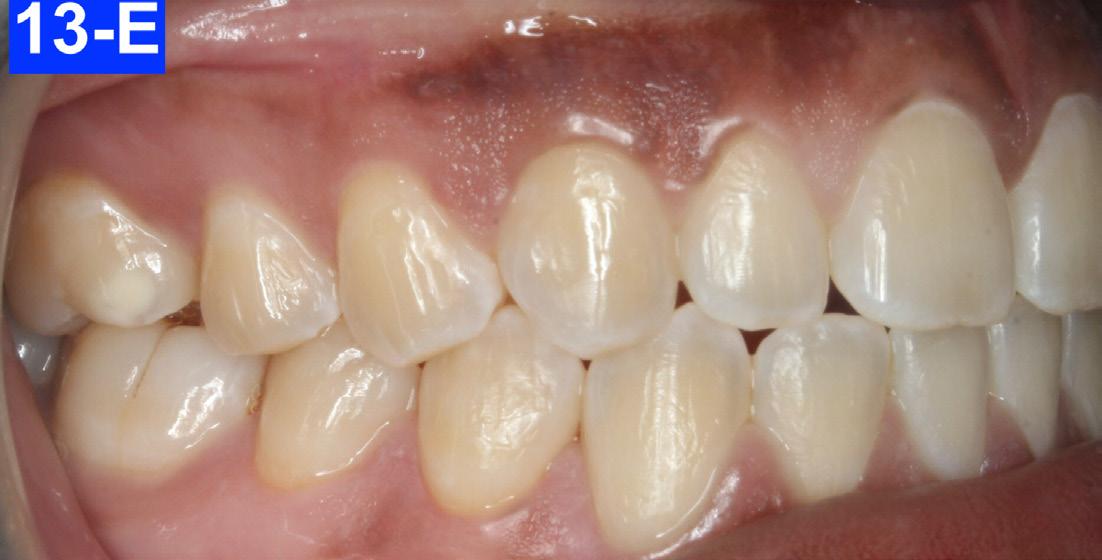

The patient reported that she had not been wearing her retainer, no longer sucked her thumb, and no longer performed the OMT exercises (Figures 13A-O).

Fig. 13-E: 3 years post-treatment, right lateral view

Fig. 13-F: 3 years post-treatment, left lateral view